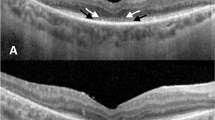

Eighty-four patients with up to -6.00 dioptres of myopia underwent photorefractive keratectomy (PRK), using 5.00 mm ablation zones. Three months post-operatively 38 (45%) complained of disturbances in night vision, compared with 21 (25%) pre-operatively. In the majority, these disturbances were regarded as negligible. However, 9 (11%) reported significant problems, defined as an inability to drive safely at night with the treated eye. At 12 months, 32 patients (38%) complained of impaired night vision, 4 (5%) of whom had significant problems. A series of measurements were performed to investigate the origins of these disturbances, especially in patients reporting significant problems. Visual impairment from forward scattered light was investigated using a computerised technique. Back scattered light was measured with a charge coupled device–camera system and a computer program was used to assess the degree of halation around a bright light source on a high-resolution monitor. Pupillary diameters were measured by infrared television pupillometry. At 6 months, those reporting a starburst effect around lights at night had small hyperopic shifts, minimal halos and high forward and back light scatter measurements. Patients who reported halo phenomena had large hyperopic shifts, little light scatter and large pupillary diameters. Of the 4 patients who reported significant disturbances at 12 months, all had persistent halo problems. Those with starburst effects in the early postoperative period noticed an improvement with time as their corneal haze gradually improved. Perturbations of night vision after PRK manifest as starbursts and halos around lights. Disturbances in corneal transparency appear to be responsible for starburst effects and are usually transient. Halos are myopic blur circles and may be persistent in a small number of individuals. All patients should be informed pre-operatively of the possible consequences of disturbances in night vision.